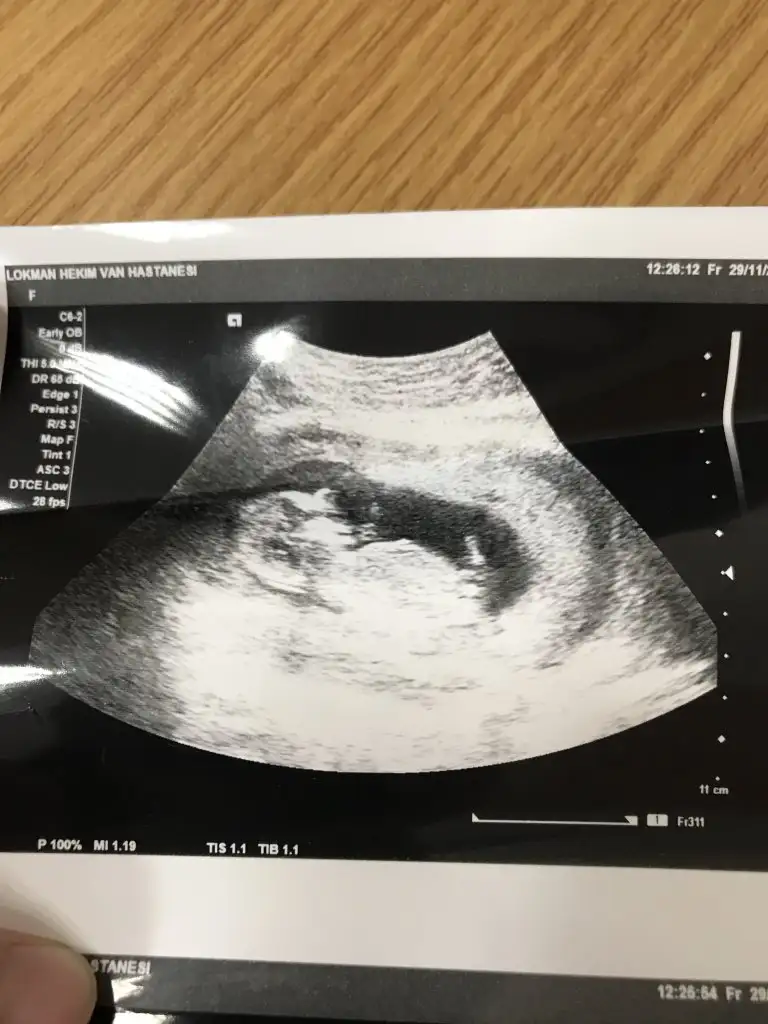

aynen bizimkide canmmBenim doktorum sağlıklı ise gebelik 3 ay yine de ilişki önermiyorum demişti. 13. Haftaya geliyor sanırım.

Fasülye gibiydi canım yuvarlak değildiKesen nasildi canim merak ettim ben de ystin gidecegim bakalim bisi der mi?